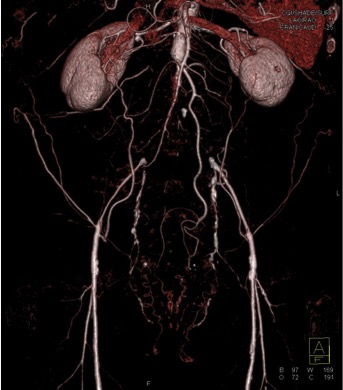

The most likely diagnosis in this case is?

acute occlusion of the aorta

sarcoma arising in the aorta

too early timing of CT Acquisition

Takayasu’s aortitis